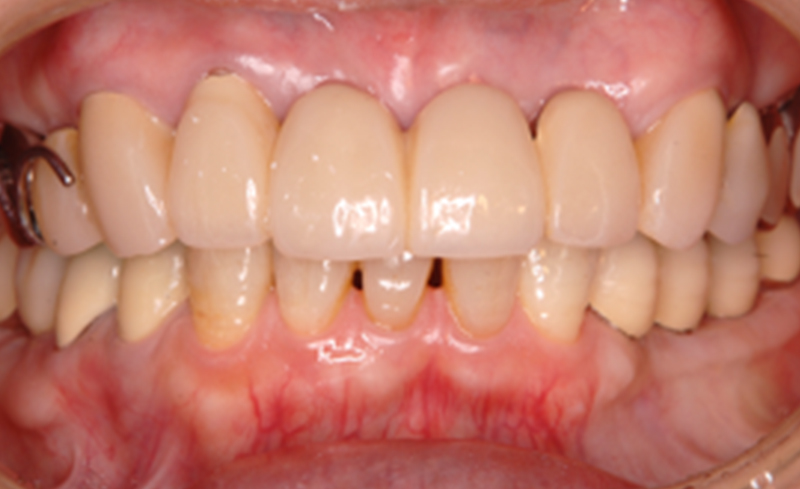

BEFORE

AFTER

| 年齢 | 63歳女性 |

|---|---|

| 治療内容 | 右下の臼歯3本と左下臼歯2本にインプラント治療を施した1例 |